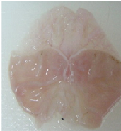

Oral administration of aqueous and methanol extracts of D. thollonii at the dose of 500 mg/kg for 14 consecutive days of treatment significantly (p<0.01) decreased the area of chronic ulcer induced by acetic acid compared with the negative control group treated with distilled water. The total surface area of 29.0±2.3 mm2in the negative control was significantly (p<0.01) reduced to 18.2±0.9 and 14.5±1.6 mm2in animals which received aqueous and methanol extracts (table 3 and fig. 3). Maalox (50 mg/kg) speeded up the healing of gastric ulcer, reducing the area of the lesion to a statistically significant (p<0.01) extent by 19.2±1.8 mm2 (33.7 %) compared to the negative control group (29.0±2.3 mm2). There were no visible signs of toxicity (change in behavior or locomotory activities, or diarrhea) in animal receiving drug (extracts, Ranitidine or Maalox) for 14 days.

Fig. 3: Macroscopic study of acetic acid-induced gastric damage in rats

In fig. 3, (a): stomach of a normal control rat: no injuries to the gastric mucosa are seen and the gastric wall is normal. (b): stomach of an ulcer control rat: there is severe destruction of the surface epithelium and necrotic lesions penetrating deeply into mucosa and submucosa layers. (c): stomach of rat treated with Maalox (50 mg/kg): the gastric wall appears normally, but sometime there is edema of submucosa layer. (d): stomach of rat treated with Ranitidine (50 mg/kg): the gastric wall appears normally with all layers. (e): stomach of rat treated with 125 mg/kg of aqueous extract: there is mild disruption of the sub mucosal layer. (f): stomach of rat treated with 250 mg/kg aqueous extract: there is moderate disruption to the surface epithelium. (g): stomach of rat treated with 500 mg/kg of aqueous extract: there is mild disruption of sub mucosal layer and edema of the muscle. (h): stomach of rat treated with 125 mg/kg of methanol extract: there is mild disruption to the epithelium surface and the sub mucosal layer and edema of the serosal layer. (i): stomach of rat treated with 250 mg/kg of methanol extract: there is mild disruption to the epithelium surface. (j): stomach of rat treated with 500 mg/kg of methanol extract: there is moderate disruption of the epithelium surface although the gastric wall appears normally.